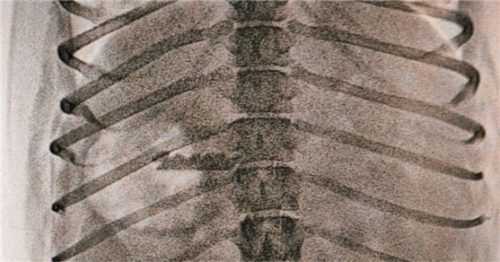

Klar erkennbar: die Rasierklinge auf der Röntgenaufnahme.

Rosenheim – In Rosenheim ist ein kleiner Hund in die Falle eines Tierhassers getappt. Nur weil das Tier später Stücke von Rasierklingen erbrach, konnte es gerettet werden.